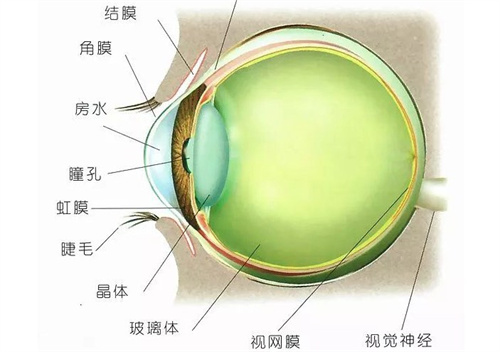

在探讨眼科疾病治疗时,眼底病的治疗备受关注,而武汉协和医院在这方面的表现值得深入了解。

很多人会问:武汉协和医院治疗眼底病好吗?下面从多个维度为大家分析。

业务开展比较靠前:作为全省亚专科门类比较齐全的眼科之一,各项可靠业务开展均在全省处于比较靠前地位。

在眼底病治疗方面,医生们能够运用可靠的技术和丰富的经验,为患者制定个性化的治疗方案。